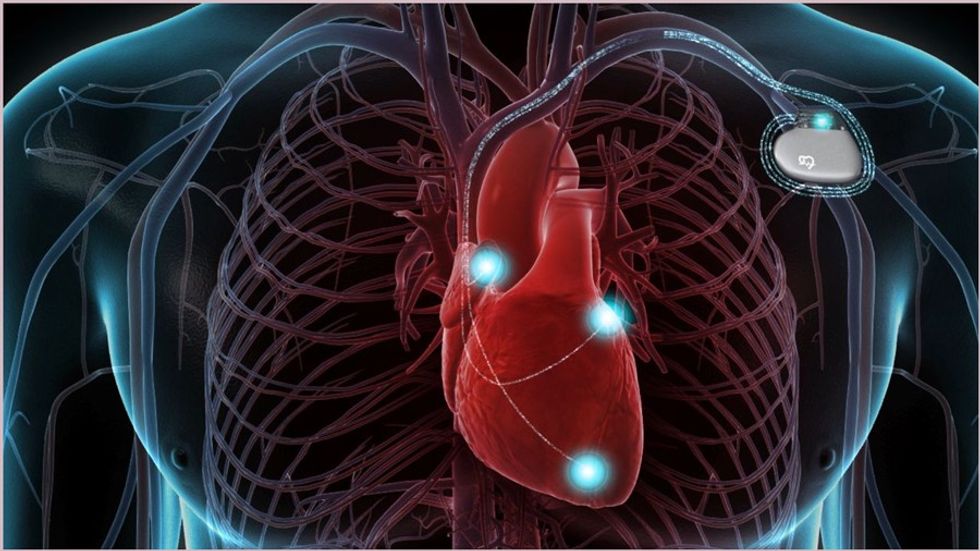

Defibrilatori kardioverter i implantueshëm (ICD) është një pajisje e vogël, e cila mund t’i trajtojë njerëzit me ritme jonormale të rrezikshme të zemrës.

ICD dërgon impulse elektrike për të rregulluar ritmet anormale të zemrës, sidomos ato që mund të jenë të rrezikshme dhe të shkaktojnë një arrest kardiak.

ICD-ja vendoset nën lëkurë, zakonisht në hapësirën menjëherë nën klavikulë për t’i monitoruar rrahjet e zemrës. Disa tela të hollë e lidhin ICD-në me zemrën dhe gjatë gjithë kohës kontrollohen të rrahurat dhe ritmi i zemrës. Monitorimi i zemrës realizohet përmes elektrodave.

Nëse ICD heton një ritëm të rrezikshëm të zemrës, mund të bëjë një apo më shumë nga trajtimet e mëposhtme:

Cakton ritmin – një seri e impulseve me voltazh të ulët elektrik në një shkalle të lartë për të korrigjuar ritmin e zemrës.

Kardioversioni – një ose më shumë goditje të vogla elektrike për të rikthyer ritmin normal të zemrës.

Defibrilacioni – një ose më shumë goditje të mëdha elektrike për të rikthyer ritmin normal të zemrës.